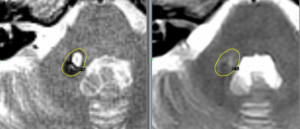

Ангиома в голове

Ангиома — доброкачественное образование, состоящее из кровеносных или лимфатических сосудов. Кавернозная ангиома (гемангиома) — сосудистая патология, чаще образующаяся врожденно либо проявляющаяся на протяжении жизни. Основа образования ангиом — патологическое разрастание кровяных и лимфатических сосудов. Чаще диагностируется заболевание у детей. Характерное отличие кавернозных патологий — интенсивный рост и расширение. Появляются образования на поверхностном эпидермальном слое и …